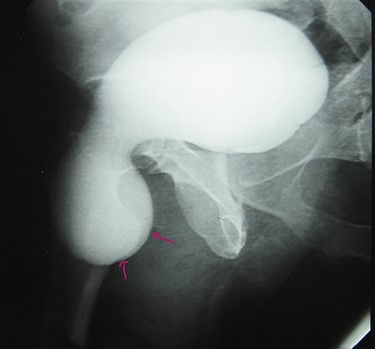

A 72-year-old man with a history of controlled diabetes and hypertension presented to our department with right inguinal swelling and intermittent lower urinary tract symptoms (LUTS) with pollakiuria, dysuria, prolonged micturition time and a sensation of a full bladder after micturition. He reported nausea, vomiting and right lower quadrant paint. The patient also reported having to manually compress the scrotum in order to empty the bladder. Physical examination revealed a slightly painful on palpation and reducible 6 cm right inguinal hernia extending into the right hemiscrotum. The body mass index of the patient was 31.4 kg/m2. His PSA was 4.3 ng/ml. On uroflowmetry, maximum flow rate (Qmax) was 13 ml/s and the voided volume was 180 cc. The uroflow curve was flat. The Bacteriological examination of urine was negative. Retrograde urethrocystography revealed right inguinal hernia containing a portion of the urinary bladder (Figs 1,2). He also had an intravenous urography in order to study the upper urinary tract and to have an idea of the renal function. This radiological exploration confirms the data of the retrograde urethrocystography and illustrates well the bladder hernia. However, a moderate left hydronephrosis with a nonobstructive pyelic calculus of 1.5 cm was observed on intravenous urography (Figs 3,4). Intraoperative findings revealed a direct right inguinal hernia with complete herniation of bladder into the scrotum. The bladder appeared healthy with no signs of injury and was restored to its normal anatomical position without resection. The hernia was repaired with a biologic mesh by the Lichtenstein technique. The patient had an uneventful postoperative course. Concerning his pyelic calculus problem, shock wave lithotripsy sessions were scheduled.

Intravenous urography: moderate left hydronephrosis and bladder addition image.